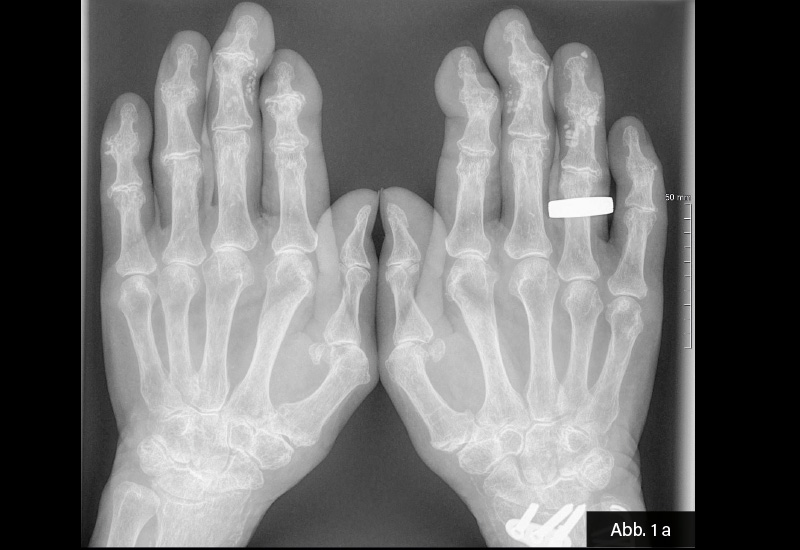

KLINISCHER BEFUND: 155 cm, 59 kg, RR 120/80, Puls 64/min. Gelenkstatus: Derbe Auftreibungen an einzelnen Fingermittel- und Fingerendgelenken im Sinne einer Fingerpolyarthrose (Heberden- und Bouchard-Typ). Haut: Calcinosis cutis, unter anderem an D IV der rechten und D III der linken Hand.

BILDGEBENDE DIAGNOSTIK: Röntgen s. u.

DIAGNOSE: Calcinosis cutis bei CREST-Syndrom

Die Bildgebung bei Calcinosis cutis dient der Erfassung und Charakterisierung von Kalkablagerungen in Haut und Subkutis. Für den Nachweis und die Ausbreitung der Verkalkungen werden häufig konventionelle Röntgenaufnahmen eingesetzt, da diese die Kalkdepots meist deutlich sichtbar machen. Die Sonografie kann kleinere Verkalkungen, ihre Morphologie sowie die Tiefe und das Ausmaß der Läsionen darstellen. Bei unklaren Befunden oder ausgedehnter Beteiligung eignet sich die Computertomografie (CT) zur exakten Lokalisierung und Quantifizierung von Kalzinosen. Die Magnetresonanztomografie (MRT) ist zum Nachweis von Kalk weniger sensitiv, kann aber hilfreich zur Beurteilung des umgebenden Weichteilstatus sein. Radiologische Methoden sind entscheidend zur Differenzierung gegenüber anderen Ablagerungsdermatosen (z. B. Ossifikation, Amyloidose).